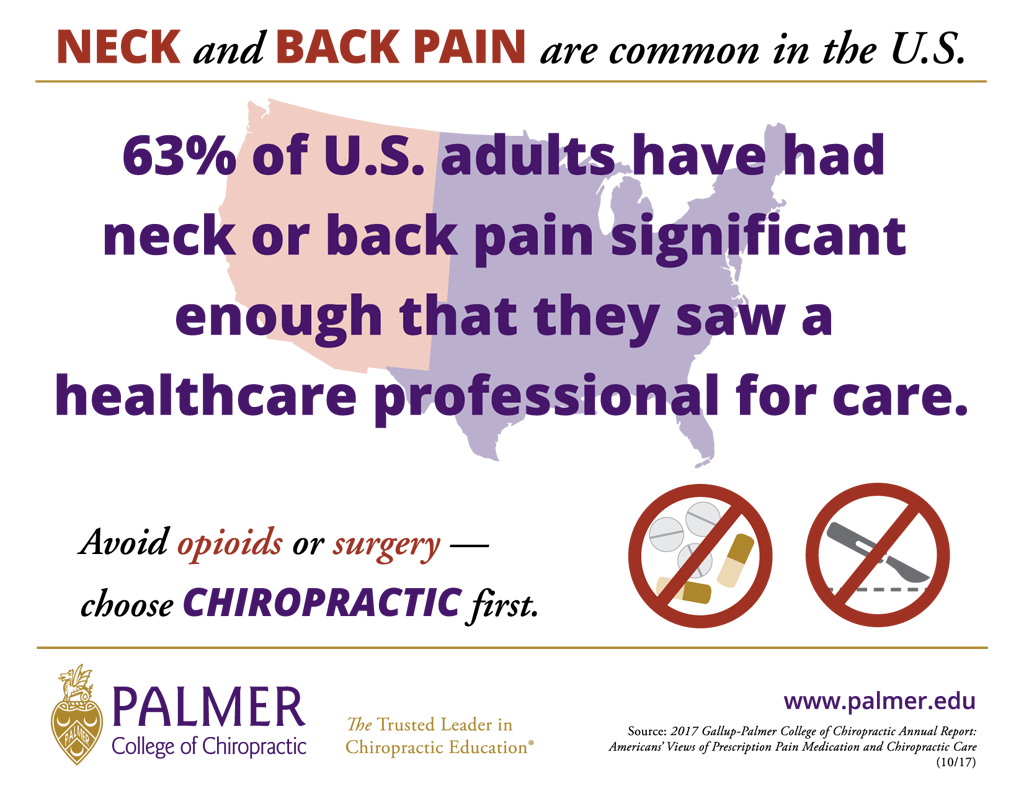

カイロプラクティックの効果と満足度

カイロプラクティックの効果と満足度

アメリカでのカイロプラクティックの認知度

アメリカでのカイロプラクティックの認知度